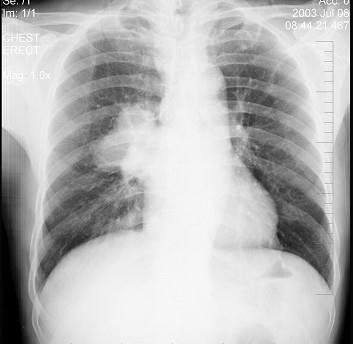

问题 男性,61岁,痰中带血就诊,X线检查如图,最可能的诊断是 ( )

选项 A.结节病 B.右肺癌 C.右肺淋巴结肿大 D.肺转移瘤 E.支气管扩张

答案 B